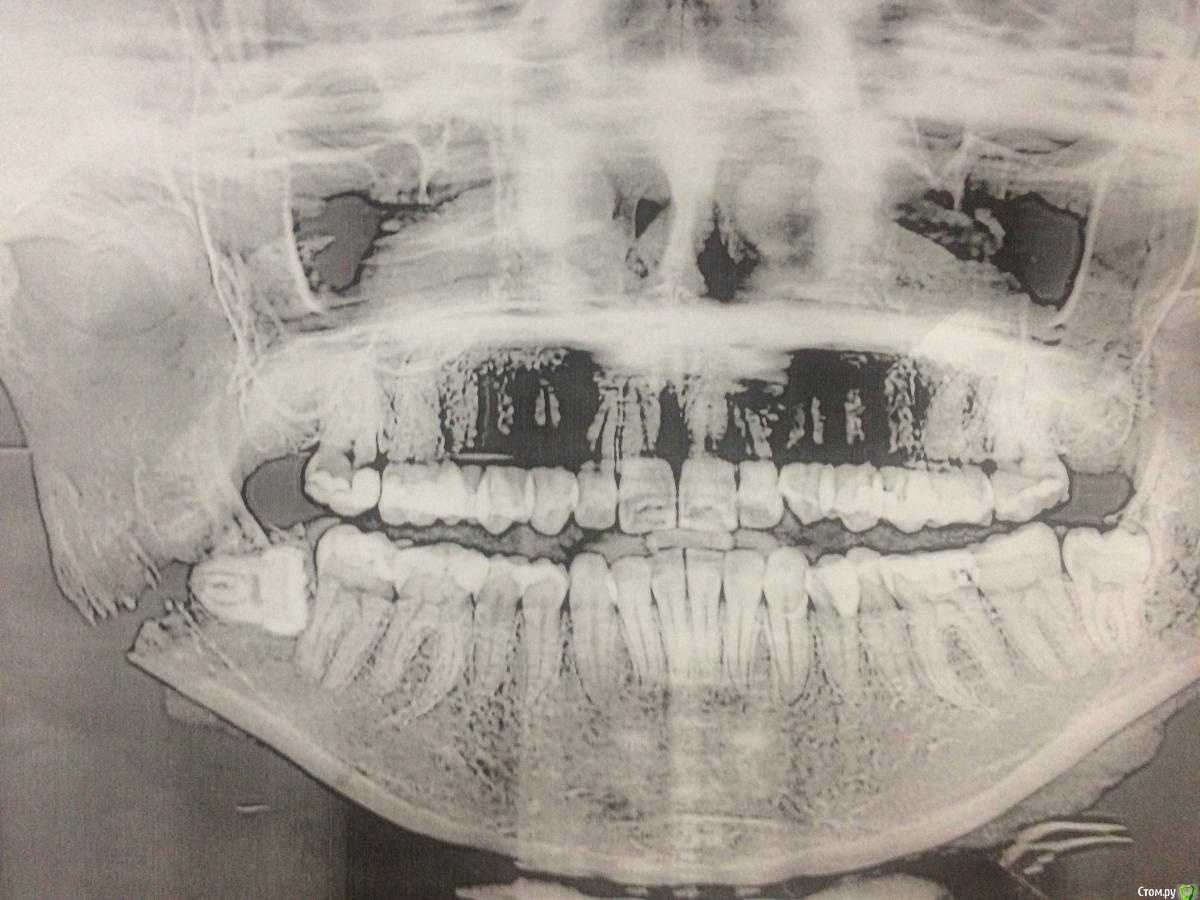

Здравствуйте, уважаемые специалисты! 10 лет назад сняла БС с верхней челюсти, удалены верхние 8-ки, нижние 8-ки пока в десне. Категорически хочу исправить ситуацию с несмыканием губ (смыкаются только напрягая подбородок), некрасивый профиль с торчащими под наклоном верхними зубами. Большинство врачей ортодонтов рекомендуют удаление верхних 4-к и засчет этого сократить щель и убрать наклон. На мои вопросы про возможные методы выдвижения вперёд нижней челюсти отвечают, что скорее всего она вернётся в старое положение так как мне уже 27 лет! Какой возможный выход вы видите в моей ситуации?

судя по вашим зубным фотографиям - щели как таковой и нет, резцы в контакте. поэтому просто удаление  верхних четверок - не исправит ситуацию

перемещение нижней челюсти и возраст - не взаимосвязаны. Но в Вашем случае она действительно не станет кпереди  - в силу своей формы и размера.

Если действительно хотите кардинально поменять профиль - рассмотрите вариант сочетания лечения с ортогнатией. Возможно только так Вы получите желанный результат?